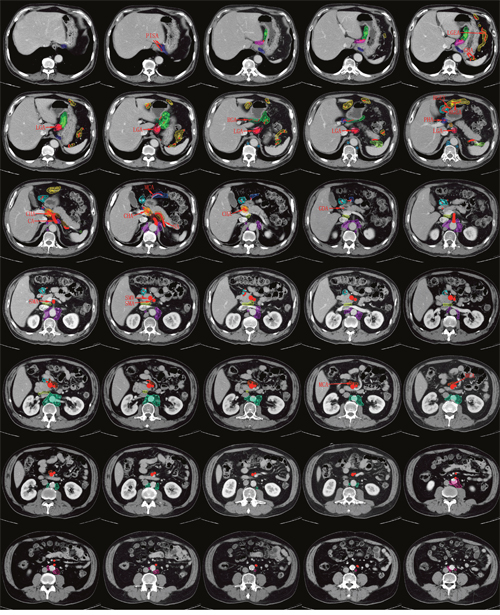

Figure 2 depicts the radiographic delineation and metastasis risk density of the 16 LN stations on a standard patient.

Figure 2: Consistency mapping of 16 lymph node stations in gastric cancer by CT-based vessel-guided delineation of 255 patients. In total, 35 representative axial CT images were selected moving in the cranial to caudal direction in 5 mm slices. PISA: phrenica inferior sinistra artery; LGA: left gastric artery; RGA: right gastric artery; GBA: gastricae breves artery; LGEA: left gastroepiploic artery; RGEA: right gastroepiploic artery; RGEV: right gastroepiploic vein; PHA: proper hepatic artery; CHA: common hepatic artery; CA: celiac artery; SA: splenic artery; MCA: middle colic artery; GDA: gastroduodenal artery; SMA: superior mesenteric artery; SMV: superior mesenteric vein.

The right pericardial LNs run along the ascending branch of the left gastric artery, located in the narrow anatomic space between the gastric cardia and liver edge, extending inferiorly by the lesser curvature LNs and in the upper part of the nodes along the left gastric artery. The high-risk metastasis region is located between the gastric cardia and the ascending branch of the left gastric artery.

The left pericardial LNs run along the corresponding esophageal branch of the left inferior phrenic artery. The volume is medial to the gastric fundus and superior to the hemidiaphragm.

The lesser curvature LNs run along the branches of the left gastric artery and along the 2nd branch and distal part of the right gastric artery, which are defined laterally by the gastric body, superiorly by the right pericardial LNs and inferiorly by the suprapyloric LNs. The metastatic risk density is higher around the branches of the left gastric artery than around the right gastric artery.

The greater curvature LNs run along the short gastric vessels, the left gastroepiploic vessels, and the 2nd branch and distal part of the right gastroepiploic artery. This LN basin is defined laterally by the gastric body and posteriorly by the spleen and splenic hilum LNs.

The suprapyloric LNs, which lie directly superior to the gastric pylorus, run along the 1st branch and the proximal part of the right gastric artery. The suprapyloric LNs are bordered on the right side by the inferior portion of the lesser curvature LNs.

The infrapyloric LNs run along the first branch and proximal part of the right gastroepiploic artery down to the confluence of the right gastroepiploic vein and the anterior superior pancreatoduodenal vein. The infrapyloric LNs lie inferior to the gastric pylorus and anterior to the pancreatic head, and the lowest level is located in the right front corner of the superior mesenteric LNs.

The left gastric LNs run along the trunk of the left gastric artery between its root and the origin of its ascending branch, the area located superior to the celiac axis and inferior to the right pericardial LNs, merging with the lesser curvature LNs. The metastatic risk appears higher on the left side and anterior to the left gastric artery than on the right side of the vessel.

The common hepatic LN station consists of a defined volume around the vessel and is bordered posteromedially by the celiac LNs and laterally by the hepatoduodenal LNs.

The area containing the celiac LNs surrounds the celiac artery, starting from its origin from the aorta to its termination, where it branches off into the common hepatic artery, the left gastric artery, and the splenic artery. Our study found that the LN basins are concentrated in the anterior half of the celiac artery.

The splenic hilar LN basin covers all the splenic hilum vasculature, lies posterior to the greater curvature LNs and posterolaterally to the spleen, and represents the area between the spleen and pancreatic tail.

The splenic artery LN basin starts from the origin of the splenic artery to the end of the pancreatic tail. The high-risk metastatic region is located in the proximal part of the splenic artery.

The hepatoduodenal ligament LNs lie along the proper hepatic artery, the common bile duct, and the portal vein and are located between the confluence of the right and left hepatic ducts and the upper border of the pancreas, in the anterior surface of the main portal vein.

The posterior pancreatic LNs lie on the posterior surface of the pancreatic head and anterior to the paraaortic LNs, extending to the portacaval space. It appears that the high-risk metastatic region is located in the higher position of this volume.

The superior mesenteric vein LNs and middle colic vessel LNs run along the surface of the superior mesenteric vessels and the middle colic vessels, respectively, inferior to the gastric wall.

The paraaortic LNs are divided into the 16a1, 16a2, 16b1 and 16b2 stations. The 16a1 station is located in the diaphragmatic aortic hiatus, on the left and right side of the aorta. The 16a2, 16b1, and 16b2 paraaortic LNs extend superiorly from the upper margin of the origin of the celiac artery to the bifurcation of the iliac artery, within the surrounding region and immediately adjacent to the aorta. Our study found that the 16a2 and 16b1 stations were most involved in LN metastasis, followed by the 16b2 station, while the 16a1 station was seldom involved.